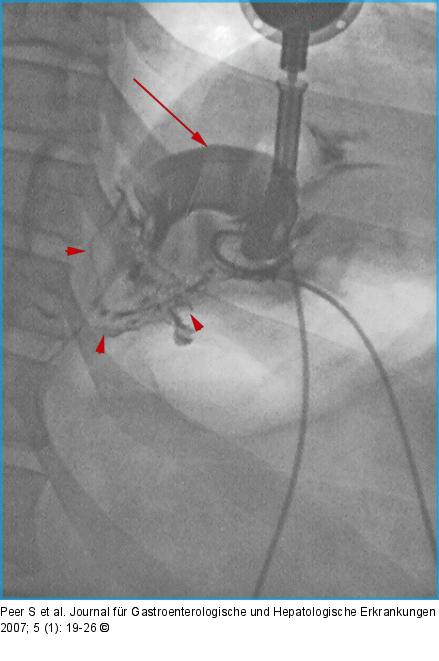

Abbildung 6: AGB Bandleck nach AGB: Partiell kontrastiertes Magenband (Pfeil) nach Anspritzen des Bandsystems. Breitflächiges Leaking am Bandrand (Pfeilspitzen). |

Bandleck nach AGB: Partiell kontrastiertes Magenband (Pfeil) nach Anspritzen des Bandsystems. Breitflächiges Leaking am Bandrand (Pfeilspitzen). |